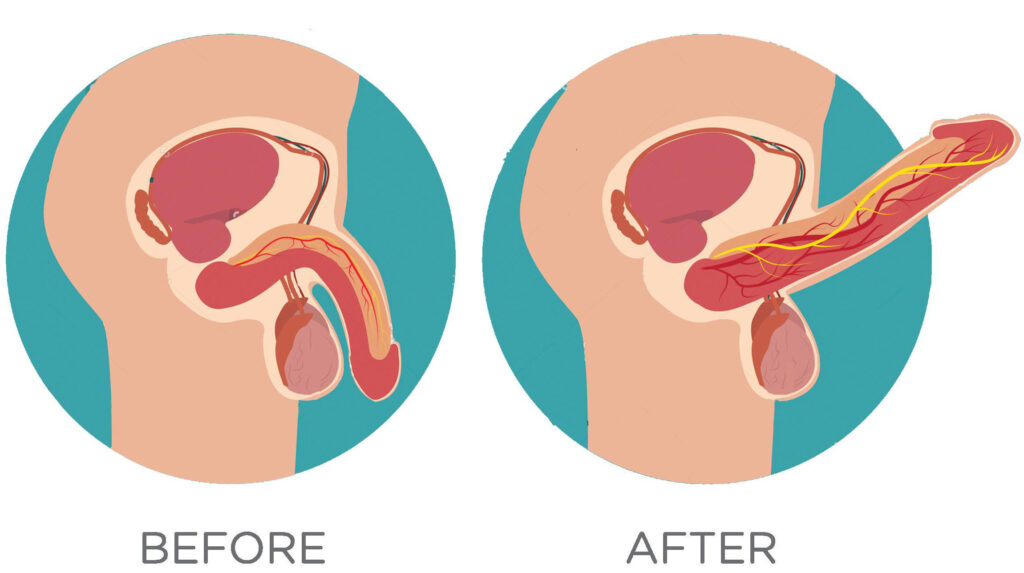

The three systems of an erection

For an erection to happen — and stay — three systems have to work together:

Blood flow in – arteries must open wide enough to flood the penis with blood.

Blood stay – tiny valves in the veins must lock shut, trapping the blood inside.

Signals from the brain – nerves must fire clearly, telling the body “now is the time.”

When these three align, you get a natural, reliable erection.

When even one fails… firmness collapses.

How they break down

Damaged blood vessels: age, stress, high cholesterol or diabetes narrow the arteries, starving the penis of blood.

Weak valves: veins can’t hold the pressure, so the blood escapes within minutes.

Silent nerves: after surgery, illness, or simply time, the nerves go numb, cutting off the vital signal from the brain.

How it works inside your body

Each gentle pulse triggers something remarkable:

New blood vessels form → increasing circulation where it matters most.

Valves strengthen → locking the blood in place, so erections stay firm.

Nerves reactivate → reconnecting the brain to the body, restoring the “signal” for desire.